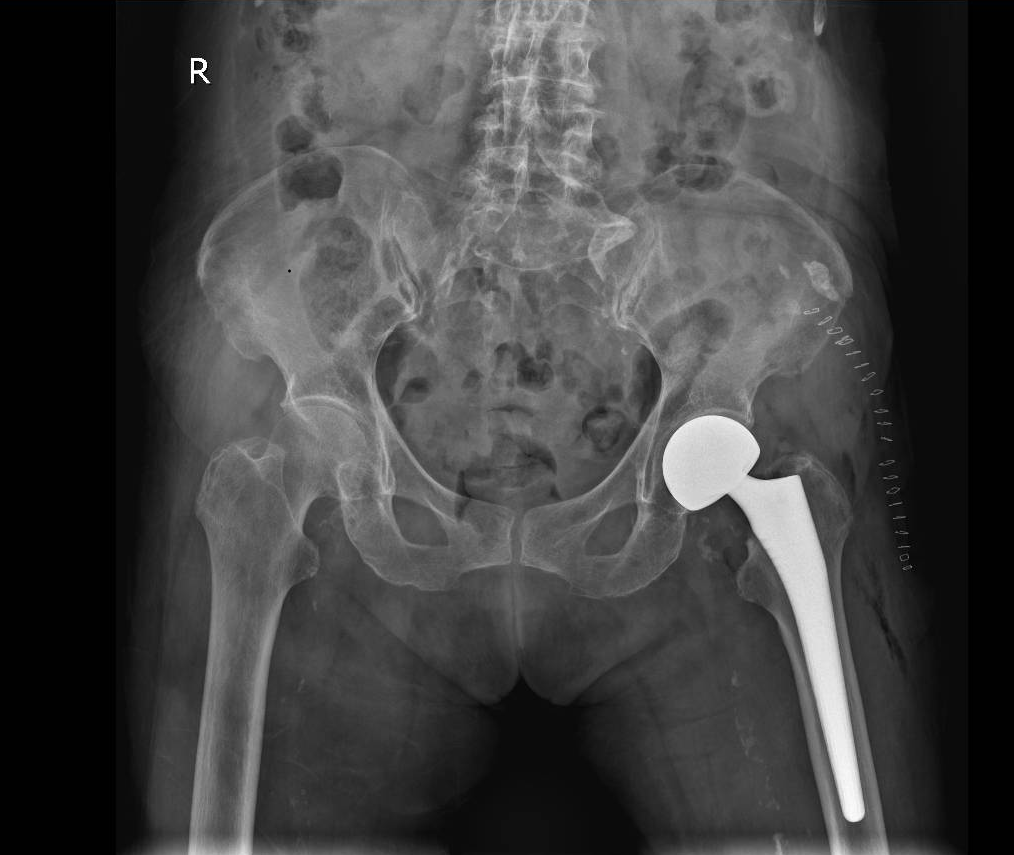

△冯奶奶术后的X光片。

莫华贵接诊后高度重视。104岁的超高龄,加上基础疾病,围手术期处理远超常规病例。科室关节外科团队再次启动多学科会诊讨论并积极治疗,专家逐一排查风险点,优化手术方案和麻醉方式,考虑冯奶奶骨质尚可,同样为冯奶奶成功实施生物型人工股骨头置换术,避免了骨水泥型髋关节置换术中可能出现的骨水泥反应、降低了血管栓塞风险、缩短了骨水泥硬化的手术时间。

“我们跑了好几家医院,都建议保守治疗,说这么大年纪手术风险太大了……”104岁香港籍冯奶奶的家属曾一度陷入绝望。冯奶奶长期居住在江门,平素生活能够自理,此次意外摔倒后,被确诊为左侧股骨颈骨折。因冯奶奶年逾百岁,且合并高血压等病史,当地医院认为手术风险过高,建议保守治疗。

手术中,医护团队默契配合,精准操作,将手术创伤降至最低。术后,护理团队依据冯奶奶的具体情况制定了个性化的护理方案,密切监测生命体征,预防感染、压疮等并发症;康复团队则根据冯奶奶的身体情况,循序渐进地开展康复训练。

术后第3天,冯奶奶便能使用助行器下地行走了,精神状态也越来越好。“真的不敢相信,104岁还能做手术,还能站起来!感谢莫主任,感谢所有医护人员,是你们创造了奇迹!” 家属激动地说,并送上了锦旗。